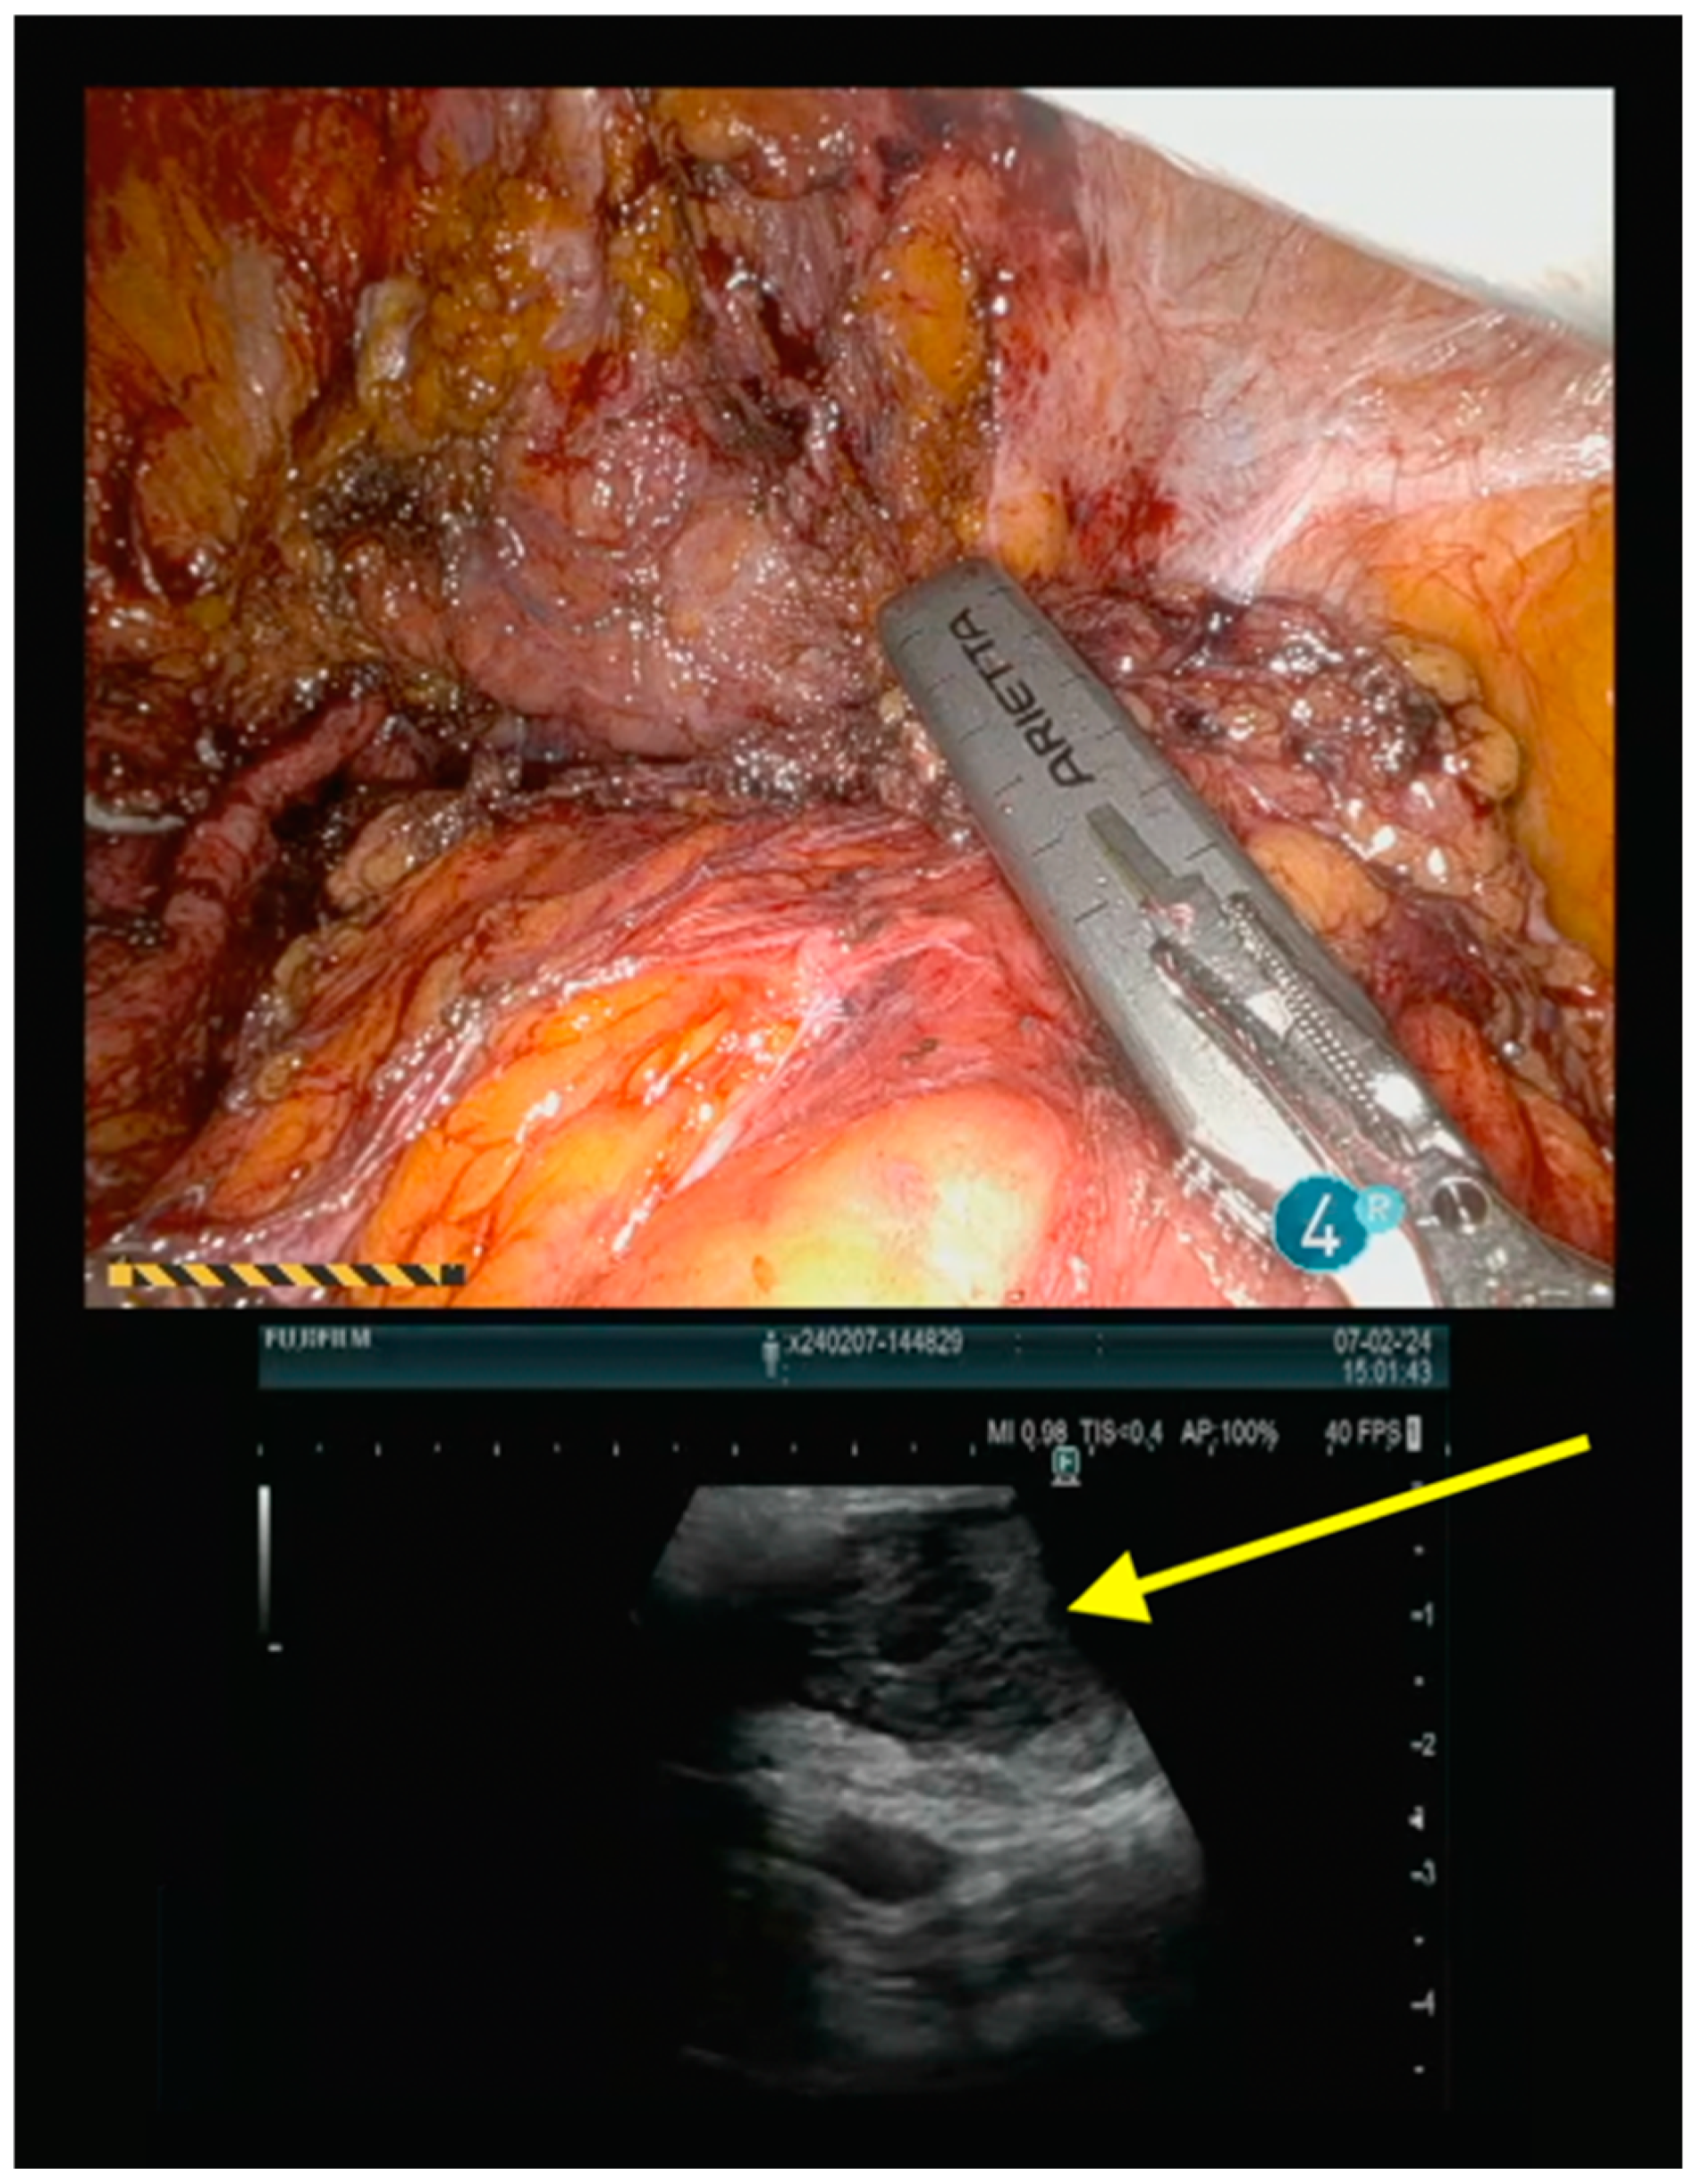

Operative Technique